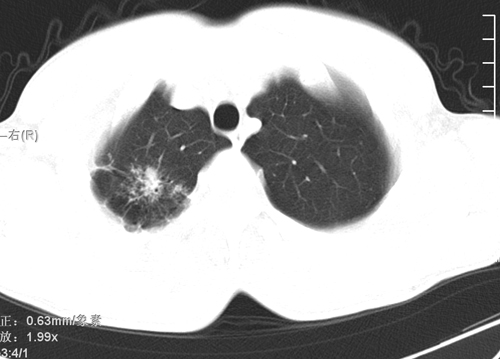

标题: CT24548:男 31 咳嗽 咯血一天 行CT检查 [打印本页]

标题: CT24548:男 31 咳嗽 咯血一天 行CT检查

ct考虑结核 但化验结果示白细胞总数 淋巴均正常,血沉7mm/h不快,请看看结核 支扩还是其他

右肺上叶尖端,后段下叶背段结核伴空洞形成

继发性肺结核伴空洞形成!

右肺继发性肺结核伴空洞形成!

好发部位+多种性质病灶=典型tb